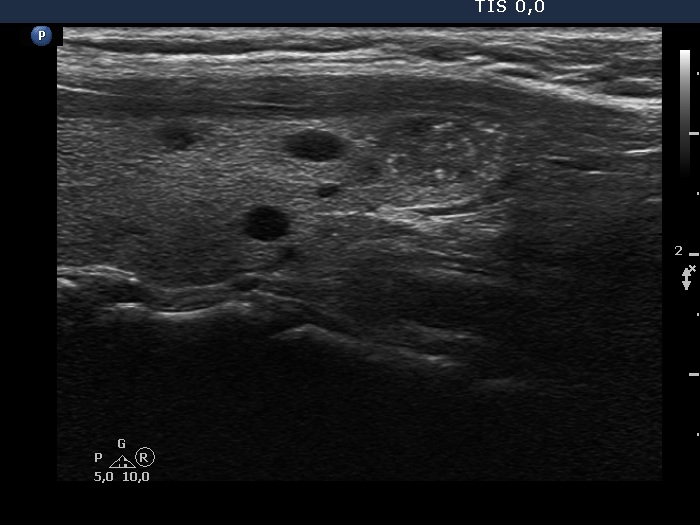

Ultrasonography. The thyroid was echonormal. Beside several hypoechoic and cystic lesions without any clinical significance, both lobes had a hypoechoic nodule. The presentation of them was very similar, both had echogenic granules and showed peripheral vascularity. However, the echogenic figures in the right nodule were probably back wall figures while those in the left nodule were microcalcifications. Regarding the vascularity, the left nodule showed perinodular blood flow while the right did not.

Comment. It is worth comparing the ultrasound presentations of the two nodules. There are small but important differences between them regarding the echogenic figures and the vascularity.